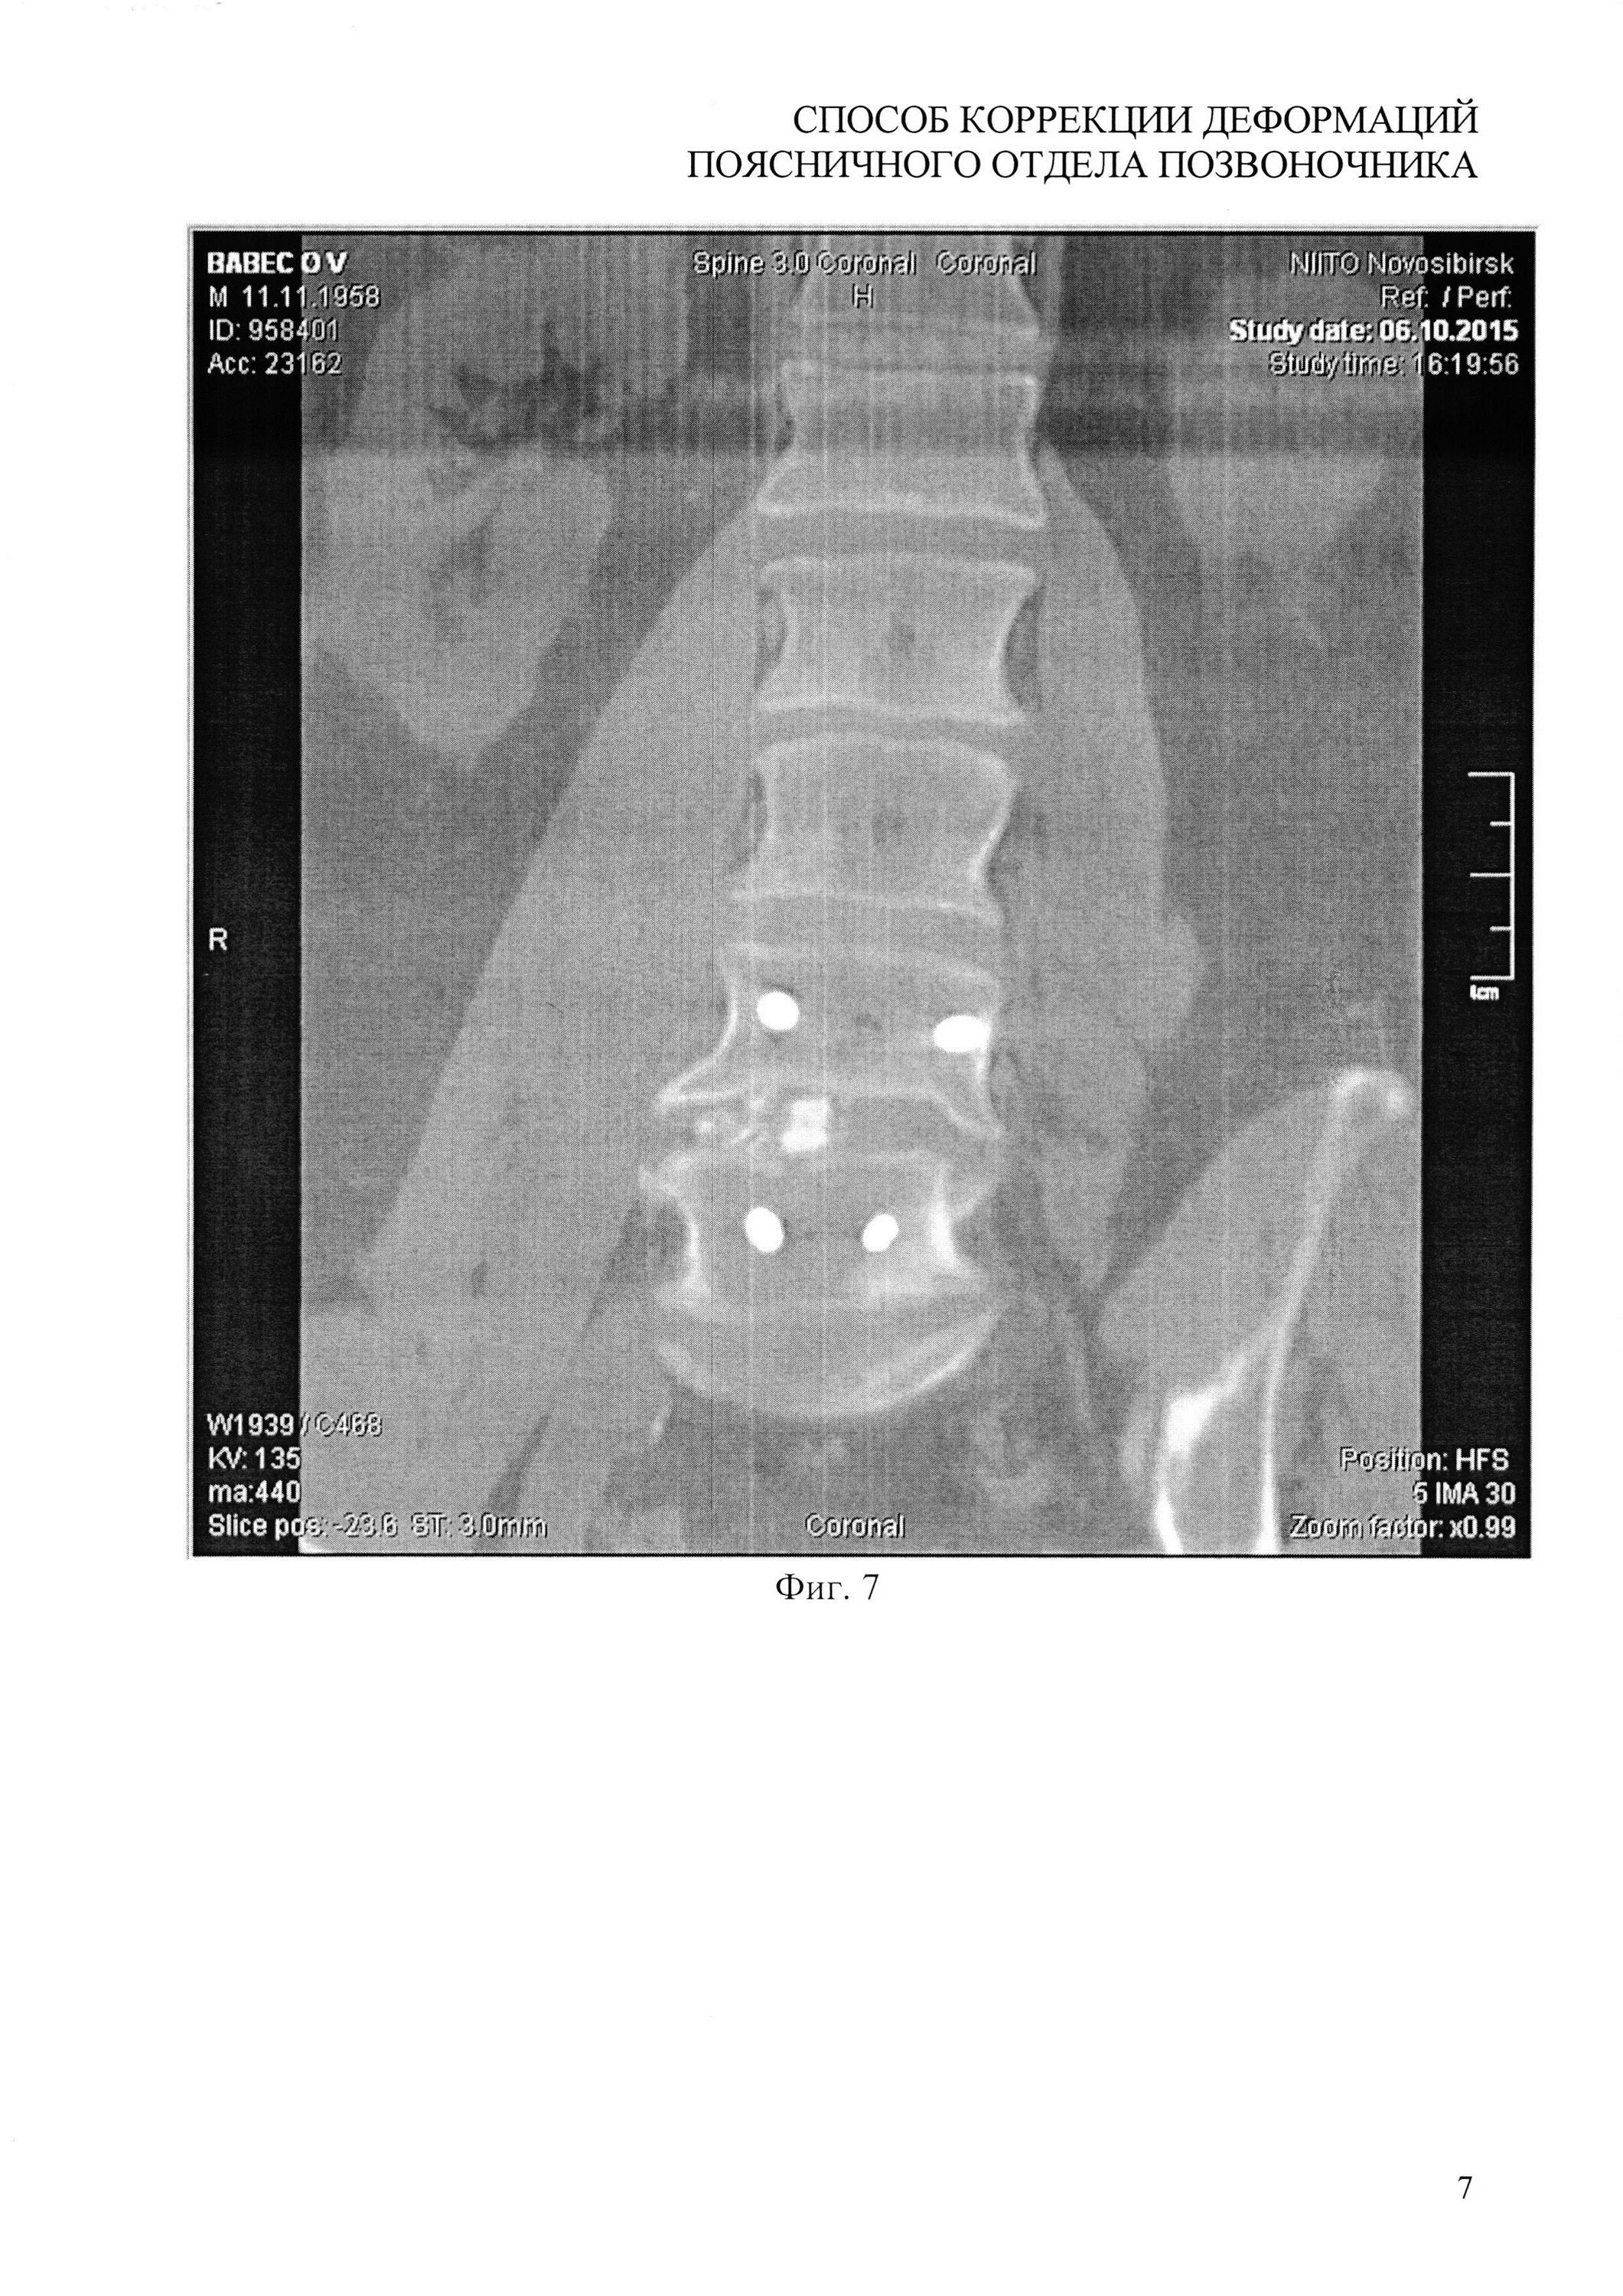

Грыжа деформирует дуральный мешок